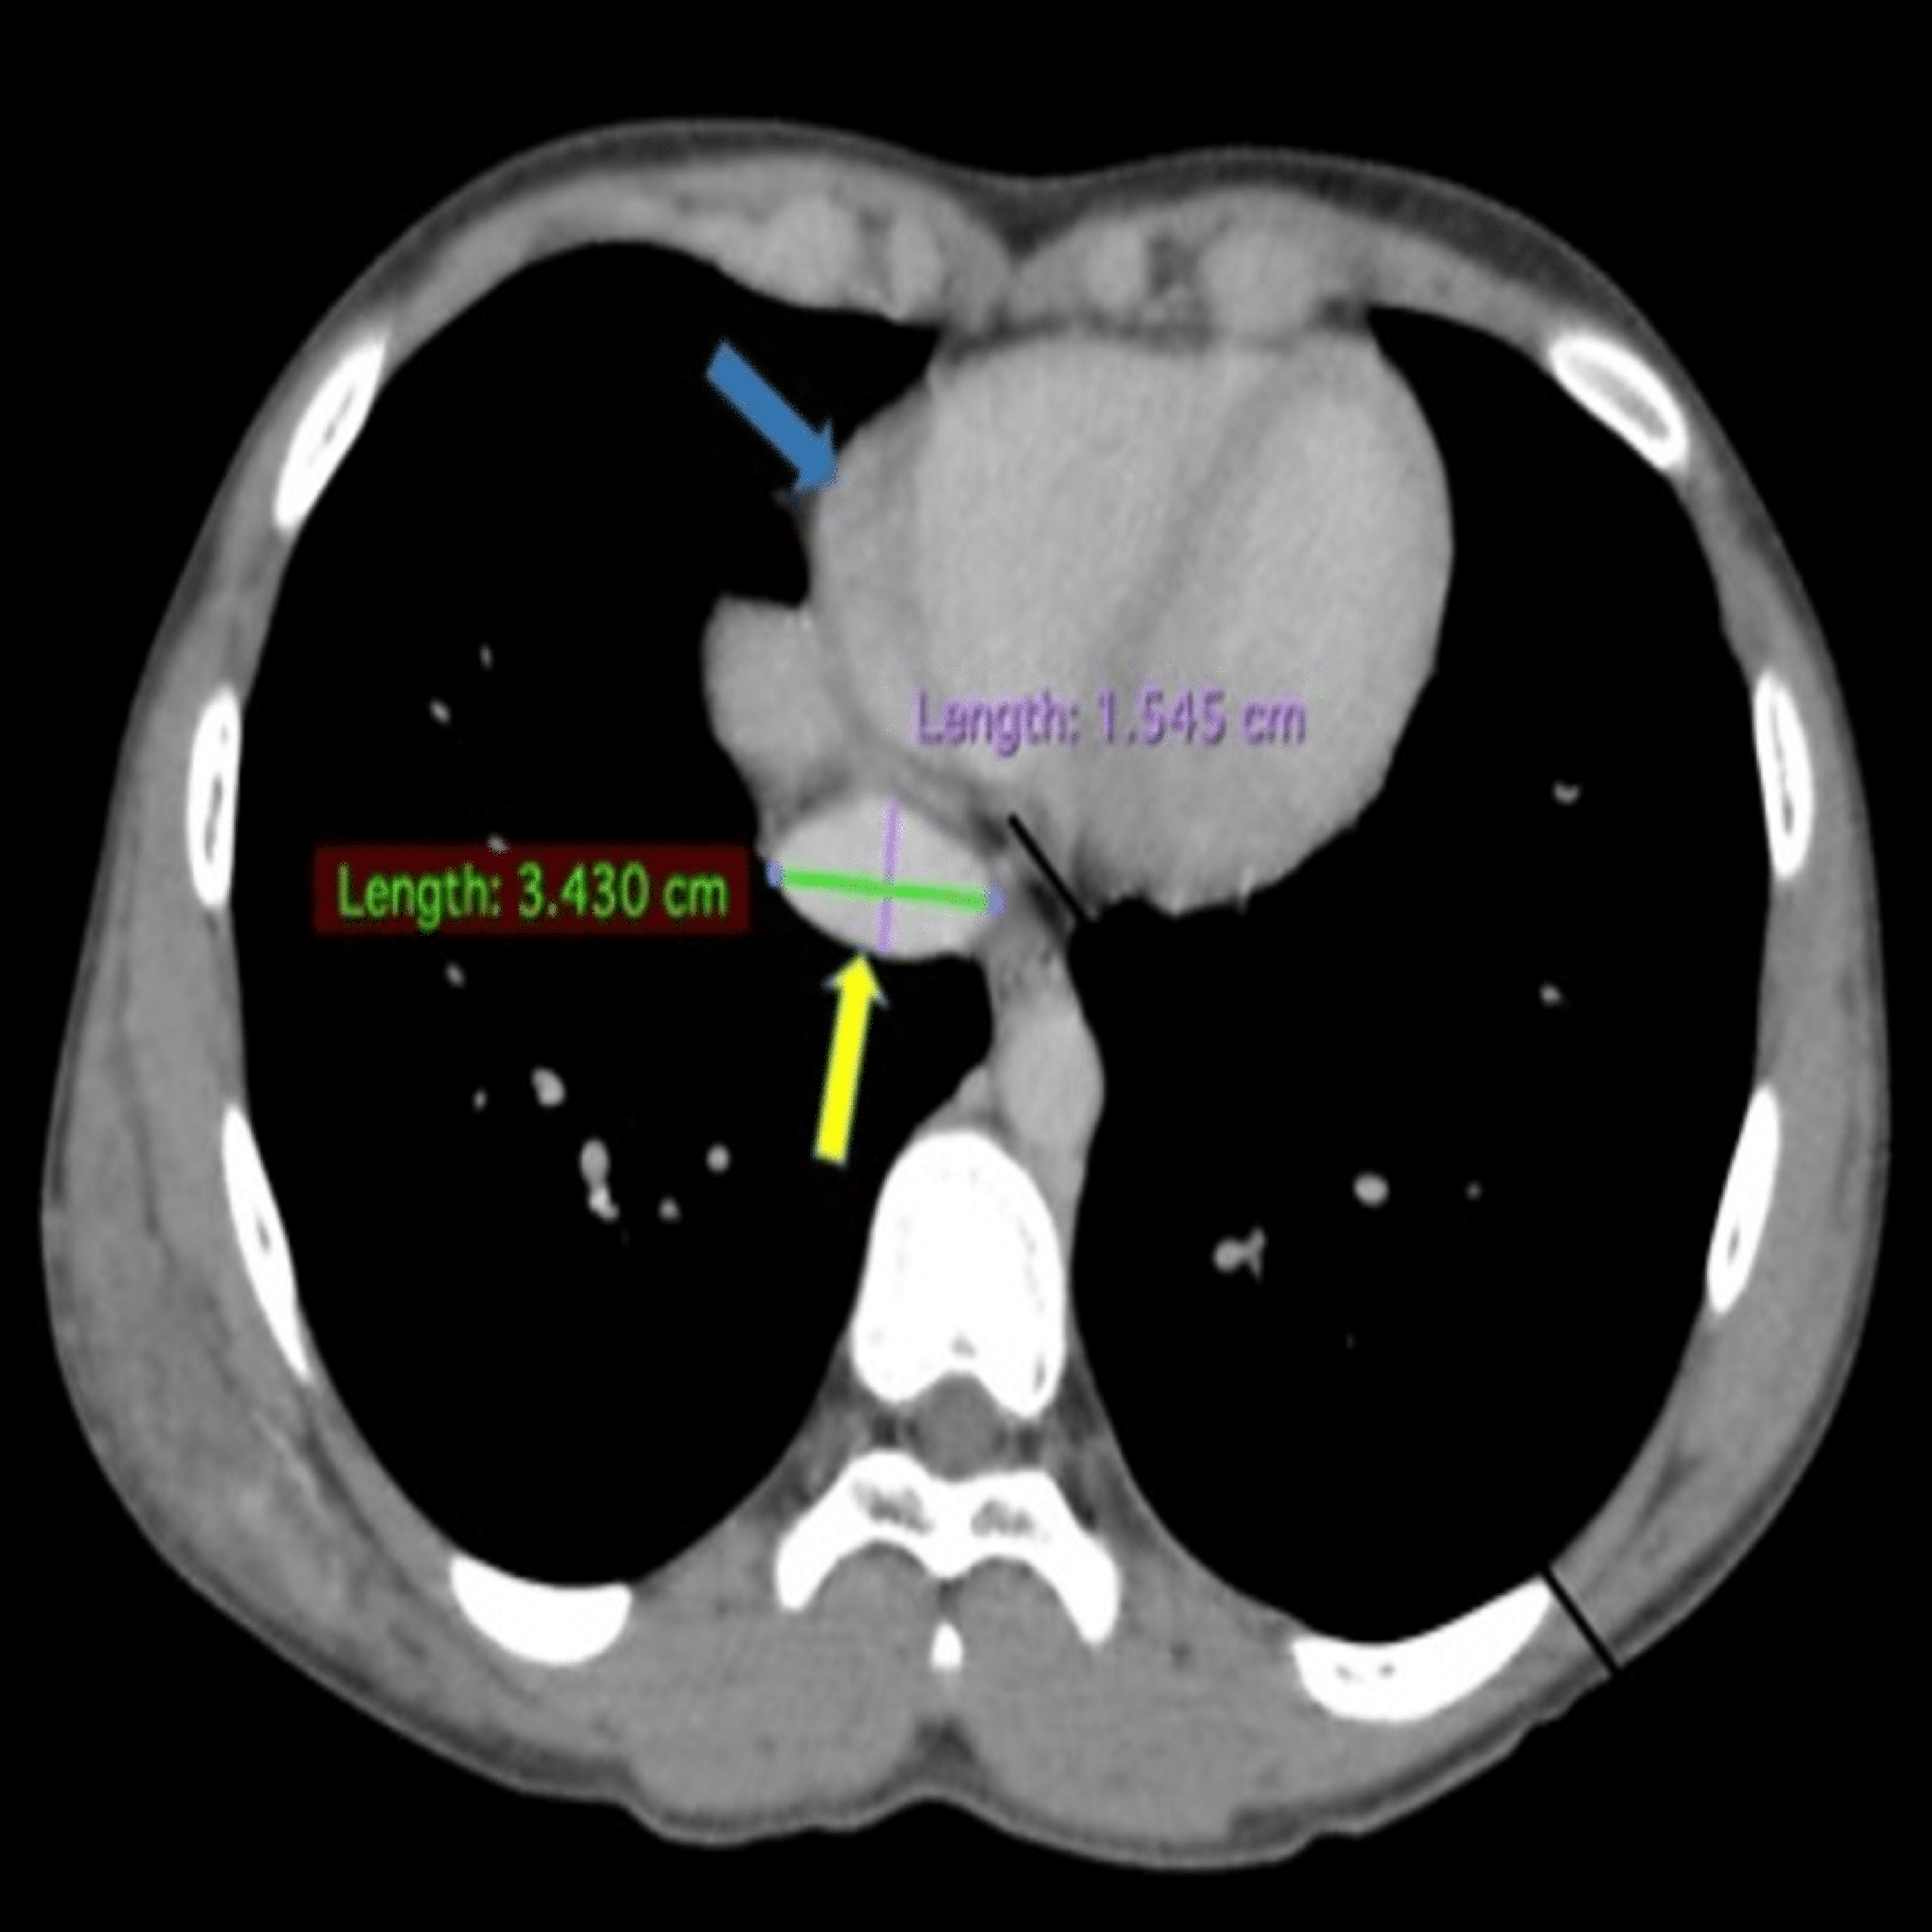

From www.semanticscholar.org

Figure 2 from Venous phase diameter of inferior venacava (IVC) on CT Normal Size Of Ivc The inferior vena cava (also known as ivc or the posterior vena cava) is a large vein that carries blood from the torso and lower body to the. It is associated with a wide variety of congenital and pathologic. Maximum ivc diameter is 1.78 cm and showed. That was normal for him. Ultrasonographic measurement of inferior vena cava (ivc) diameter. Normal Size Of Ivc.